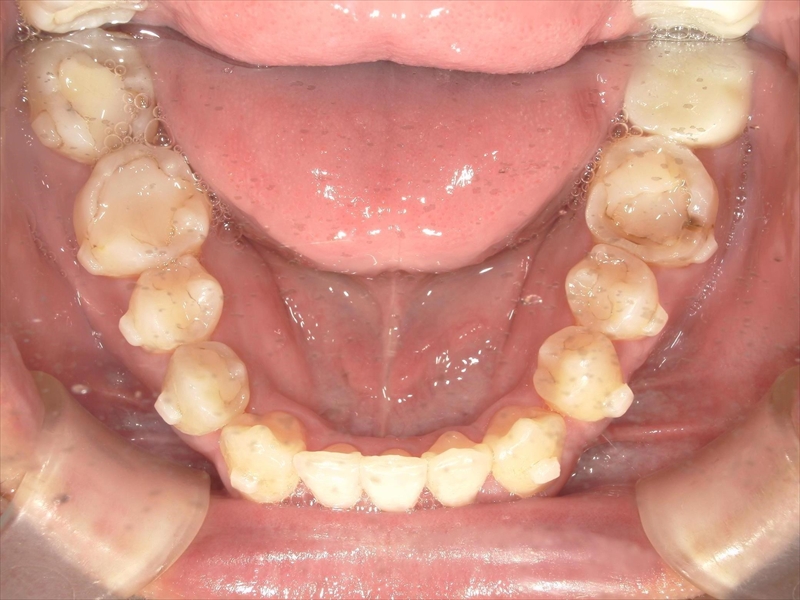

上の歯は歯が並ぶスペースが足りず、八重歯を含むガタガタした歯並びになっていました。

下の歯は、受け口気味で、さらに右下の前から2番目の歯が1本足りない状態でした。

治療前後 写真